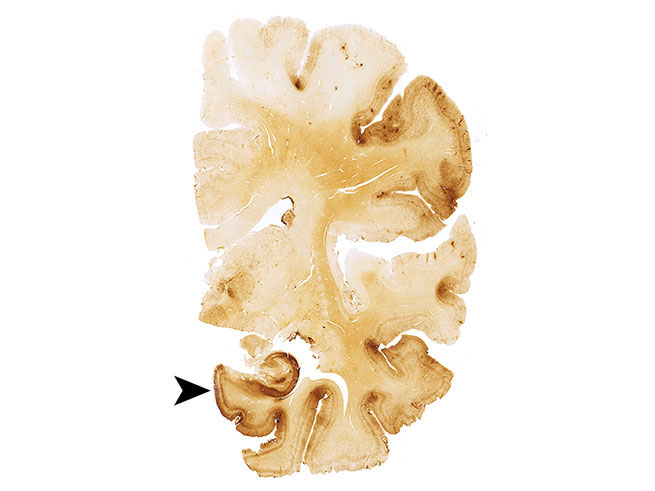

CTE in a former football players' brain

A former NFL player with stage IV CTE. The brown areas indicate tau protein clumps, a hallmark of the disease. JAMA/McKee et al.